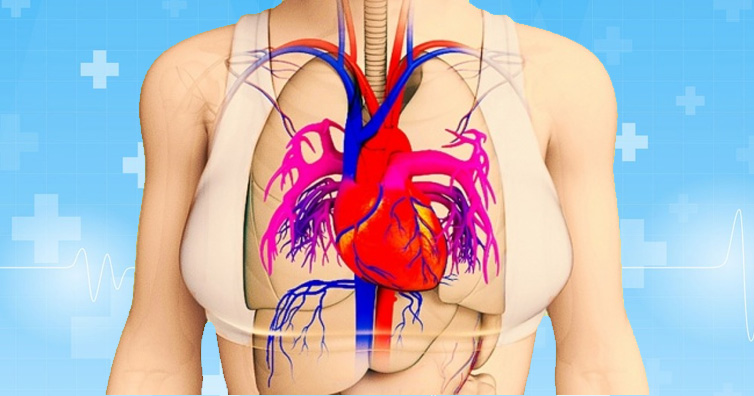

Your body constantly gives you signals before a heart attack. You should be smart enough to recognize them. If you do not acknowledge them, you are only increasing the risk.

According to a report, over 90 million Americans suffer from some of the other form of heart disease. Without an adequately functioning heart, the rest of the body organs are doomed to fail.

There are signals that your body gives you a month before you might even have a heart attack. Watch out for these signs and kindly do not ignore them.